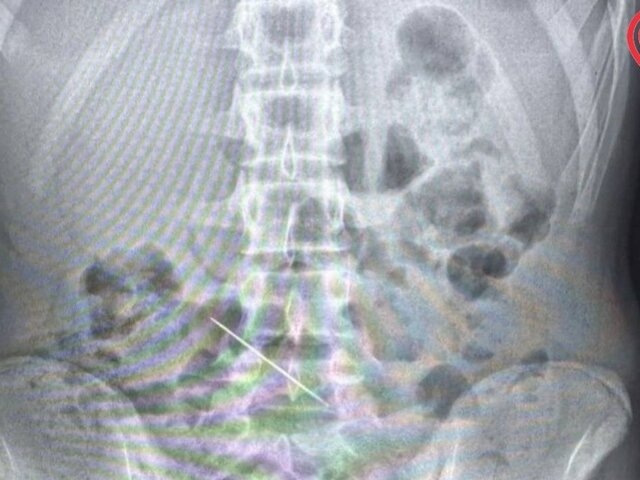

В Москве хирурги спасли ребенка, проглотившего швейную иглу

Фото: департамент здравоохранения Москвы/

Мальчика, испытывавшего острую боль в подреберье, экстренно госпитализировали из-за подозрения на аппендицит. По итогам обследования специалисты медучреждения выяснили, что причиной дискомфорта стала 5-сантиметровая швейная игла. Инородный предмет застрял в поперечной ободочной кишке и проткнул ее.

В ходе операции по извлечению объекта врачи обнаружили небольшое отверстие размером в 2 миллиметра, располагавшееся в месте стояния иглы. Металлический предмет выступал ушком в просвет брюшной полости – брыжеечной части кишки, где более толстая стенка.